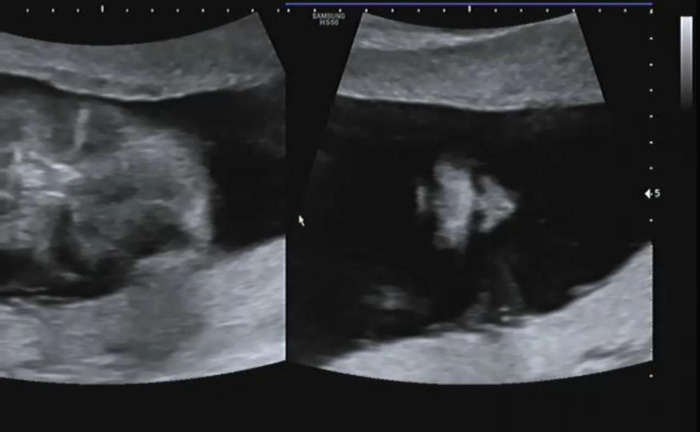

세밀하게 장기를 확인하고 태아의 척추와 갈비뼈들이 잘 형성되고 있는지 확인했다. 21주에는 일반적으로 태아의 머리 엉덩 길이(CRL)가 16~18cm인데 작은 크기임에도 내 품에서 생명이 싹트고 있음을 다시 깨닫게 되었다.